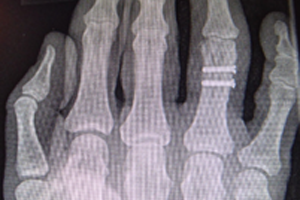

Diagnose: Mehrfragmentfraktur am Ringfingergrundglied rechts (s. Abb. 1)

Die Klägerin war gestürzt und hatte sich die rechte Hand verletzt. Die ärztliche Erstversorgung erfolgte am Unfalltag in der beklagten Klinik. In den Röntgenaufnahmen der rechten Hand wurde eine Mehrfragmentfraktur am Ringfingergrundglied diagnostiziert, die 10 Tage später offen reponiert und mit 2 Schrauben osteosynthetisch stabilisiert wurde.